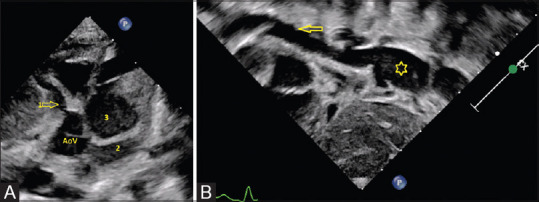

川崎病,传统上被归类为中血管血管炎,以优先累及冠状动脉而闻名。罕见情况下,可能累及全身大动脉并影响预后。在这里,我们报告了一个婴儿川崎病,他广泛累及大血管,如腹主动脉和四肢的中血管,并伴有巨大的冠状动脉瘤。

Kawasaki disease, traditionally classified as medium vessel vasculitis, is known for the preferential involvement of coronary arteries. Infrequently, large systemic arteries might be involved and may affect the prognosis. Here, we present an infant with Kawasaki disease who had extensive involvement of large vessels such as the abdominal aorta and medium vessels of the extremities, along with giant coronary artery aneurysms.